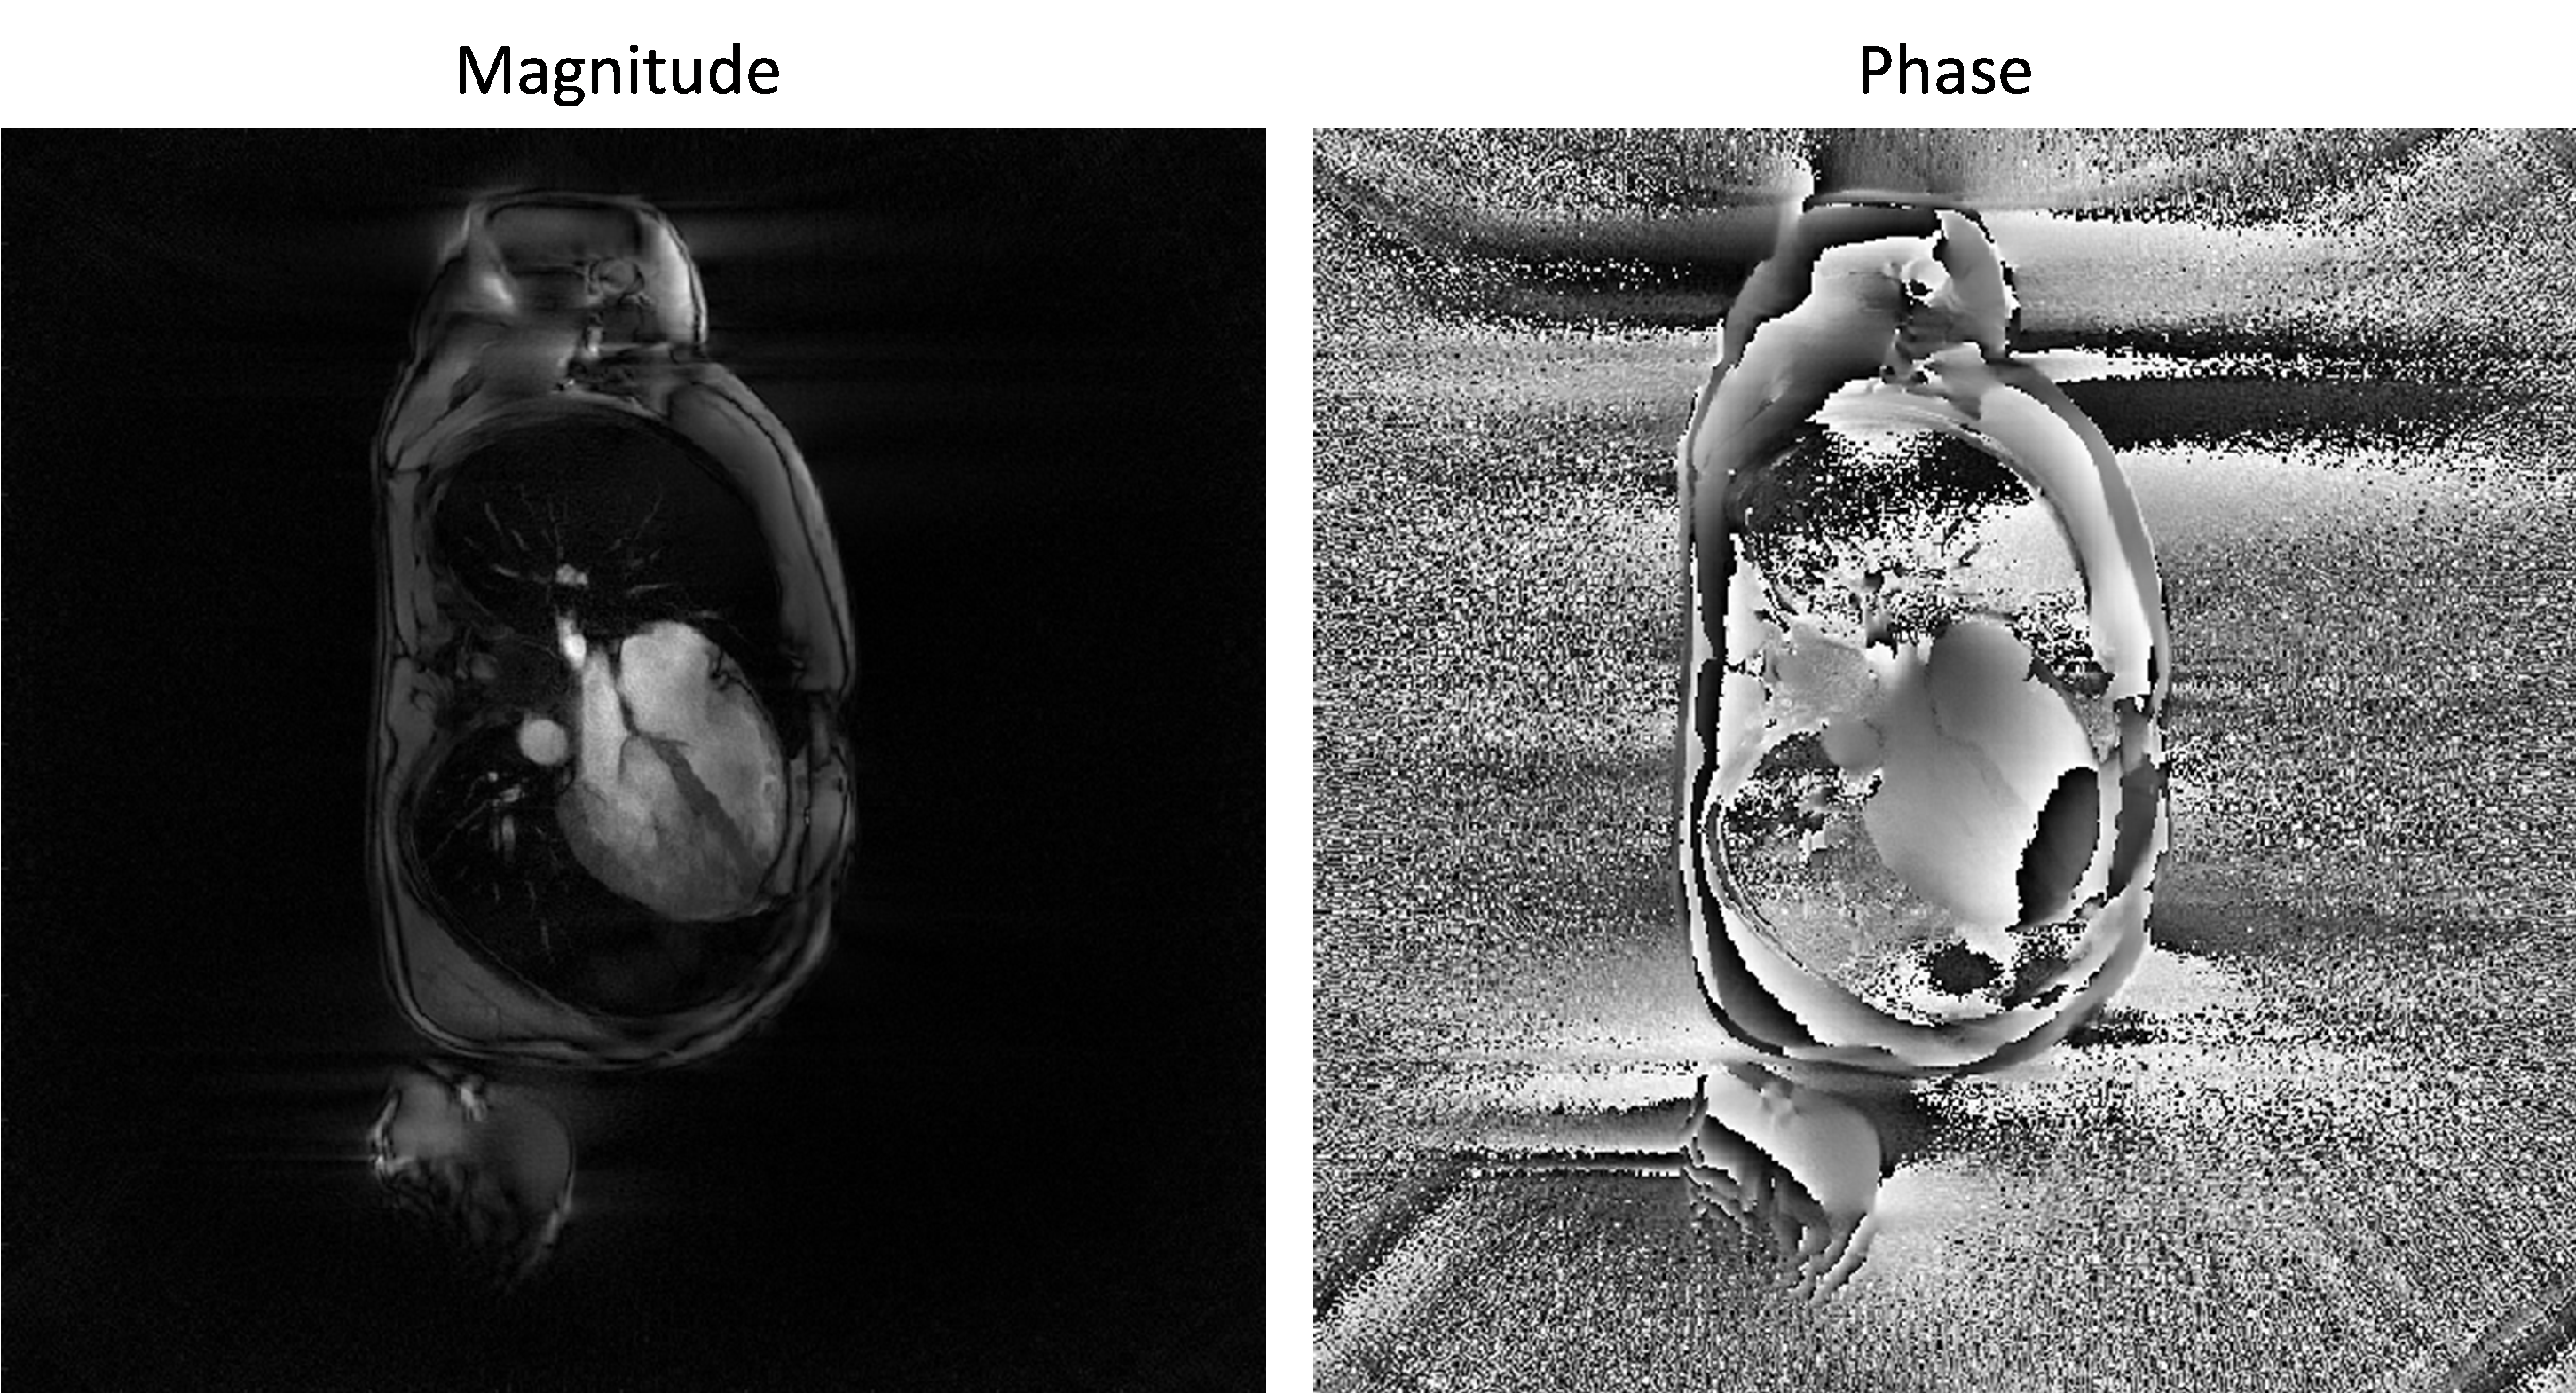

The obtained image is the a coil-combined image of all coil-images obtained at step 2 and its magnitude and phase looks as follows:

_images/magn_phase_demo_1.png